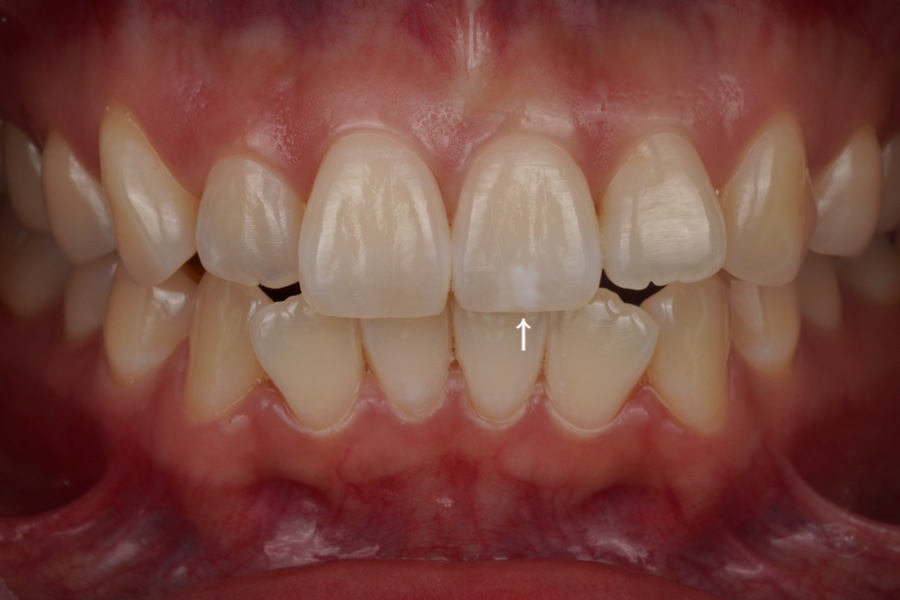

반점치 (화살표)

이번에 오신 분은 <반점치>가 고민이라

웨딩 촬영 직전에 저희 치과에 오셨습니다.

반점치는 이렇게 하얀 색으로

치아에 반점이 선천적으로 생기는 질병인데요

신경이 쓰이신다면 치료를 받아야죠